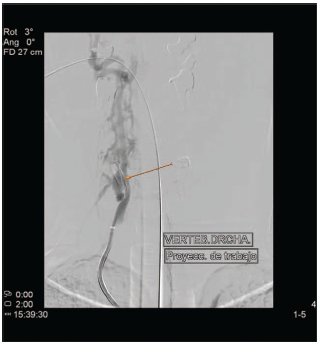

Figura 1 Angiografia con tomografía computerizada de la arteria vertebral derecha. La flecha indica el punto de la fístula arteriovenosa vertebro-vertebral con sobrecarga del plexo venoso paracervical.

Con el diagnóstico de fistula arteriovenosa directa de alto flujo de localización vertebro-vertebral en el segmento V2 derecho con sobrecarga de las venas del plexo periraquídeo vertebral cervical y drenaje final en la vena yugular interna, se programo para tratamiento endovascular. Este se realizó dos días más tarde bajo anestesia general, accediendo por vía femoral para cateterismo selectivo de la arteria vertebral derecha y embolización mediante espirales de platino con oclusión completa de la fístula sin complicaciones. A las 24 horas la enferma refirió la desaparición del soplo y el resto de la sintomatología, permaneciendo hasta la actualidad asintomática.